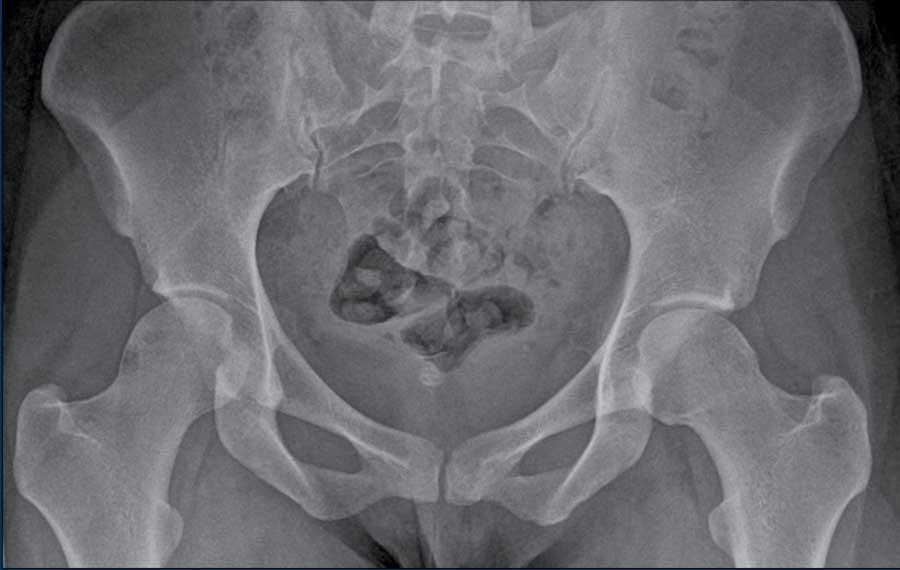

Đây là chi tiết của một X-quang Khung chậu tư thế thẳng (AP).

Trước tiên hãy quan sát kỹ hình ảnh.

Findings

- Dấu hiệu giao chéo – phần trên của thành trước ổ cối (đường đỏ) kéo dài ra ngoài vượt qua thành sau ổ cối.

- Dấu hiệu thành sau – thành sau nhô ra phía trong so với trung tâm của chỏm xương đùi.

- Dấu hiệu gai ngồi – gai ngồi nhô vào trong nhiều hơn bình thường (đường màu xanh).

Những

phát hiện này phù hợp với hình thái kẹp toàn bộ do nghịch chuyển ổ cối.

Notice that there is also some cam-morphology.